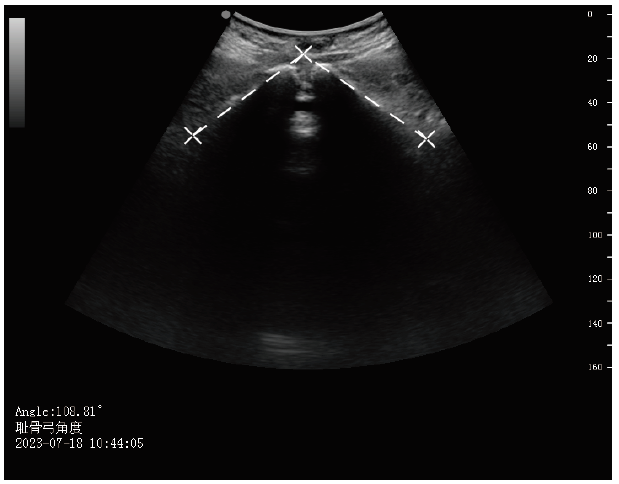

入院后采用广州莲印医疗科技有限公司wEye6产时超声系统在进行骨盆评估时同步完成,探头型号5C2AN,频率3~5 MHz。产妇测量时排空膀胱,采取仰卧位,双腿屈曲。将探头表面横向放置于产妇外阴,轻轻分开阴唇,获得盆底矢状面图。此时,耻骨联合和尿道位于视图前方,肛门位于后方。取耻骨联合下缘中点作为参考点,旋转轴面直到正中矢状面出现。图像中可观察到耻骨降支的全长,测量其夹角,见图1

图1 SPA的超声测量图像

Figure 1 Ultrasound assessment image of SPA